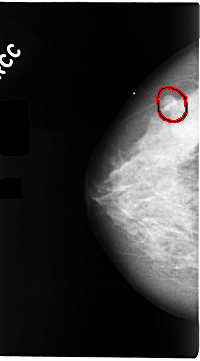

C_0104_1.LEFT_CC

LEFT_CC LINES 4736 PIXELS_PER_LINE 2624 BITS_PER_PIXEL 12 RESOLUTION 50 OVERLAY

FILE: C_0104_1.LEFT_CC.OVERLAY

TOTAL_ABNORMALITIES 1

ABNORMALITY 1

LESION_TYPE MASS SHAPE IRREGULAR MARGINS SPICULATED

ASSESSMENT 5

SUBTLETY 5

PATHOLOGY MALIGNANT

TOTAL_OUTLINES 1

BOUNDARY